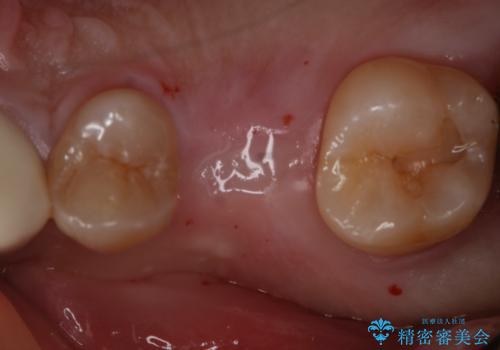

- 右上6番の歯の欠損部の治療を希望され来院された患者様です。

インプラント治療を希望されたので、インプラントとセラミッククラウンでの治療を計画しました。